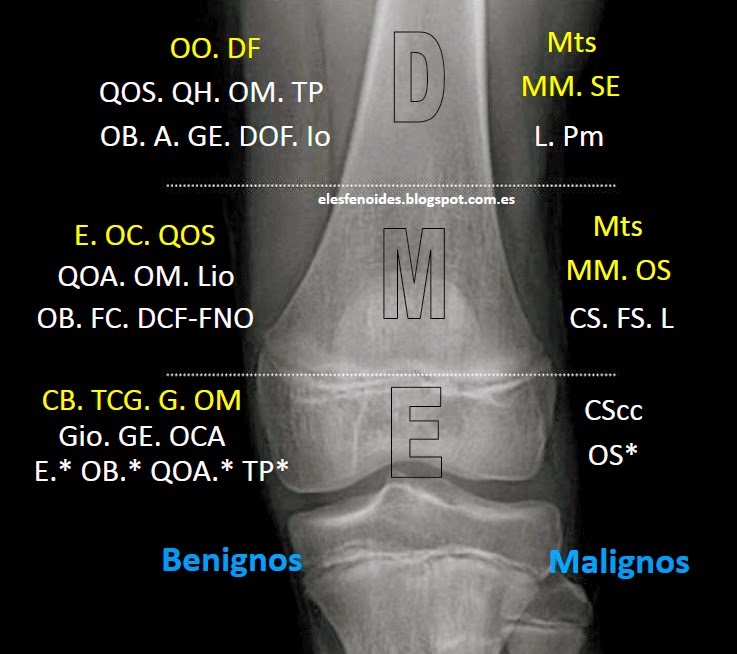

Evaluación Radiológica de tumores oseos 😈